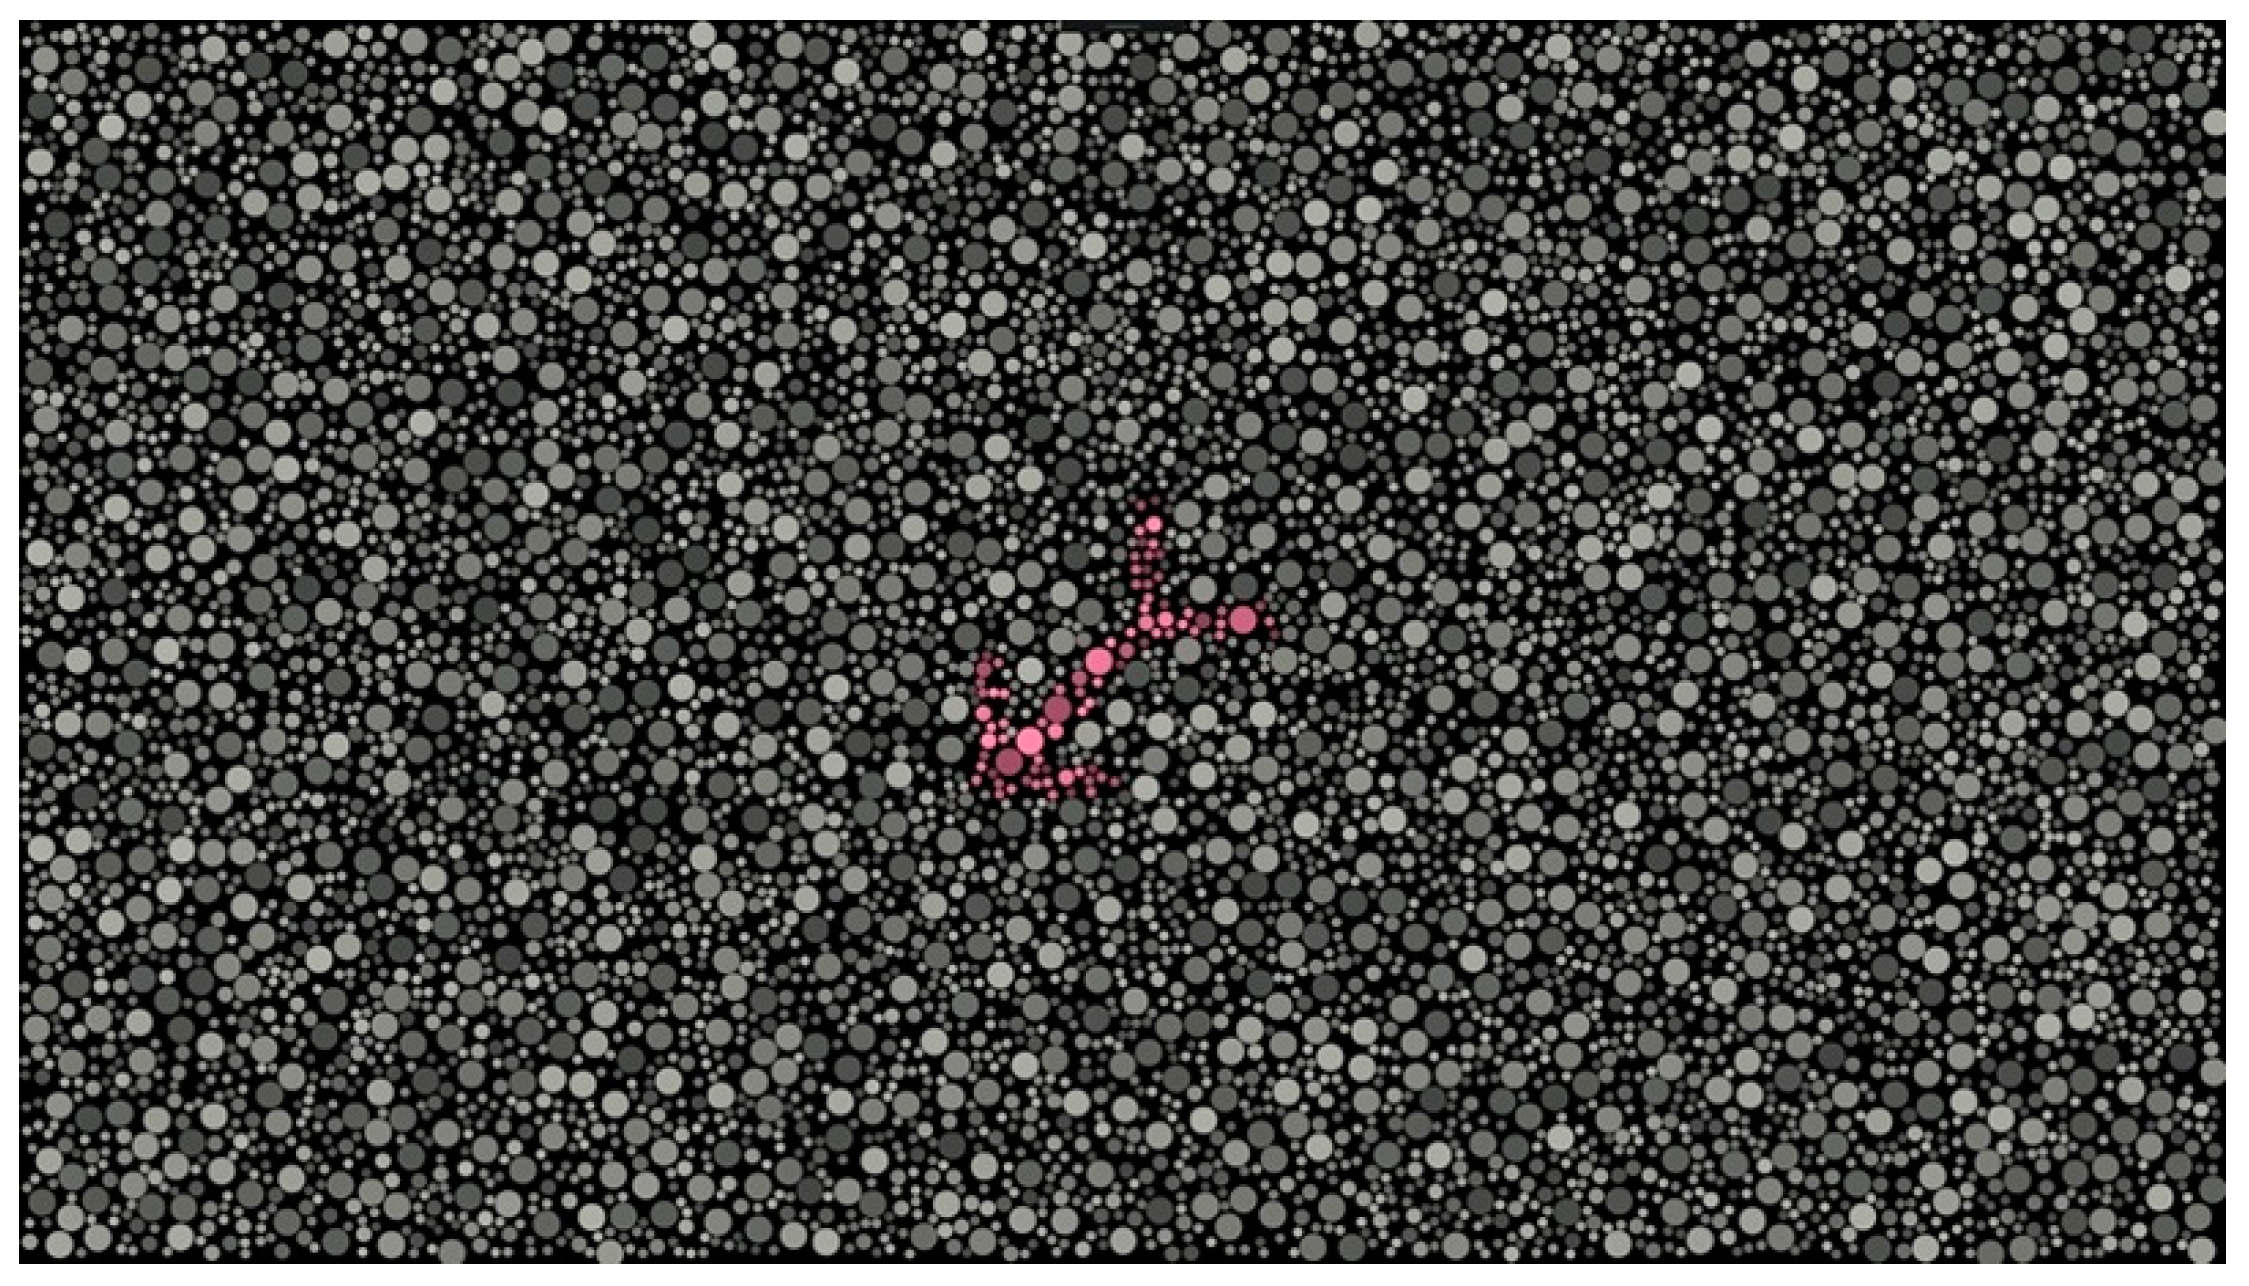

DIVE Color Test